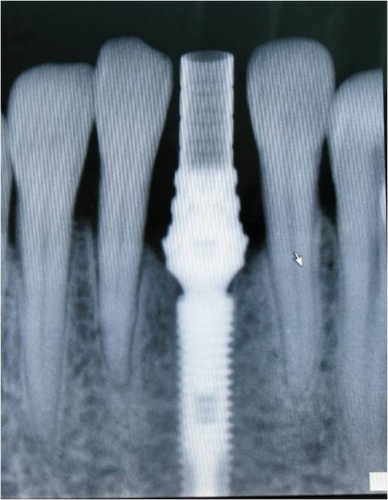

Caso 1 - Implante imediato após extração do dente fraturado (dente 11) e implante imediato

![]() |